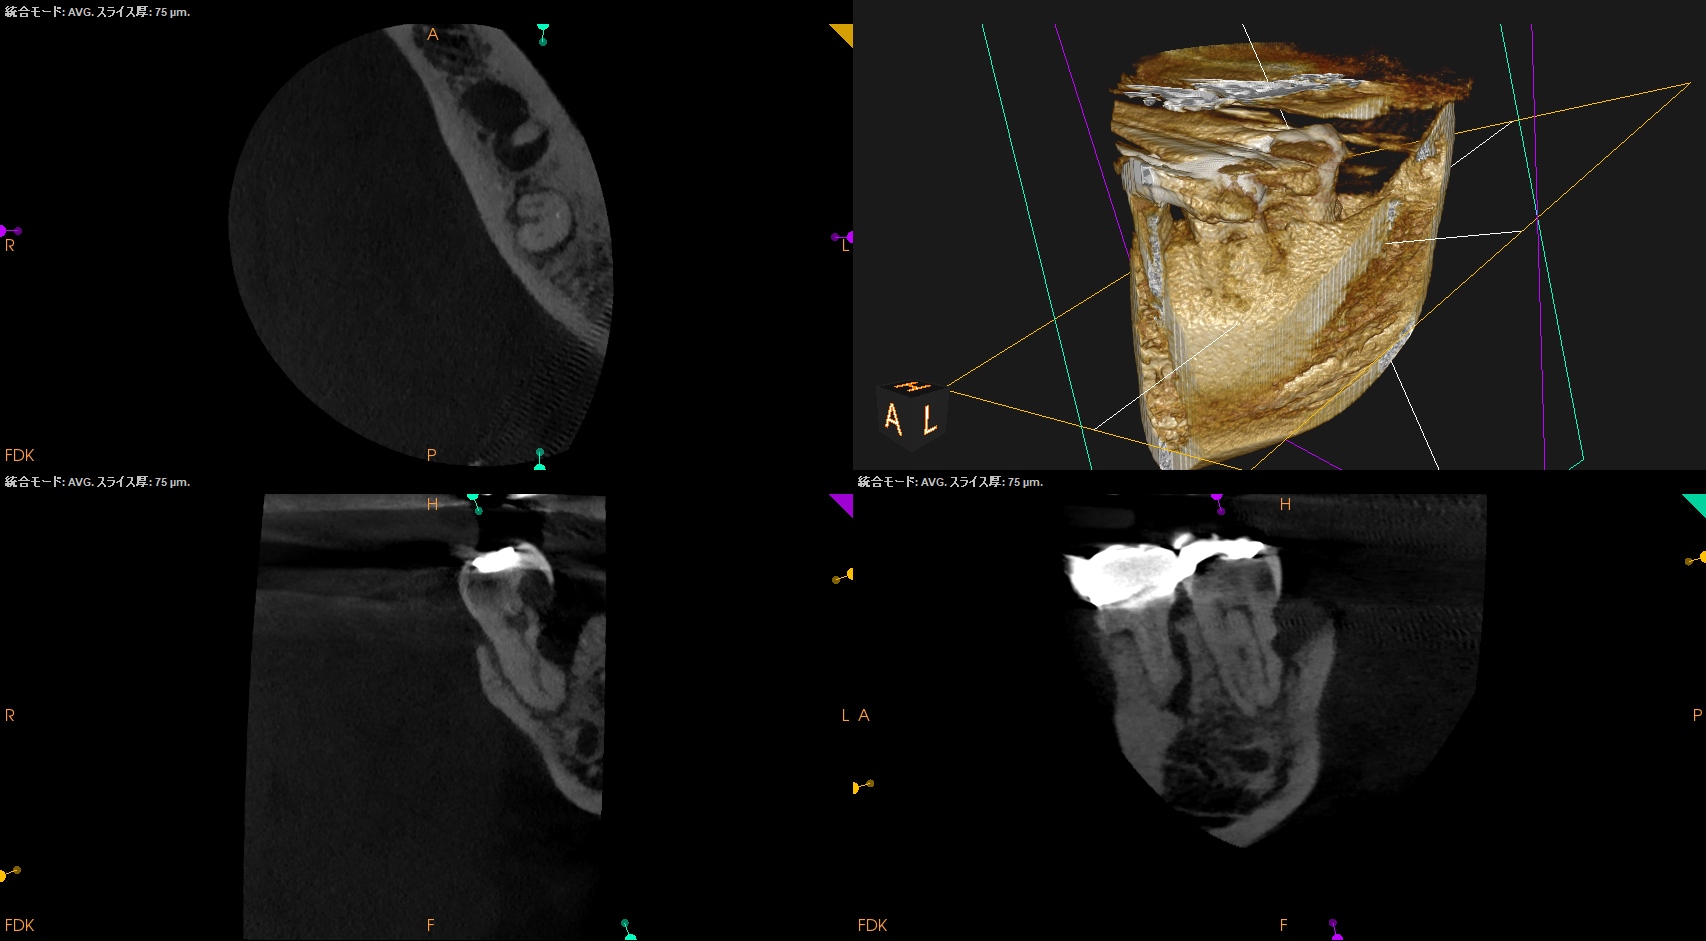

CBCT(2025.12.10)

ML

MB

D

遠心方向から見ると、

絶望的な状態であることがわかる。

PA, CBCTを撮影した。